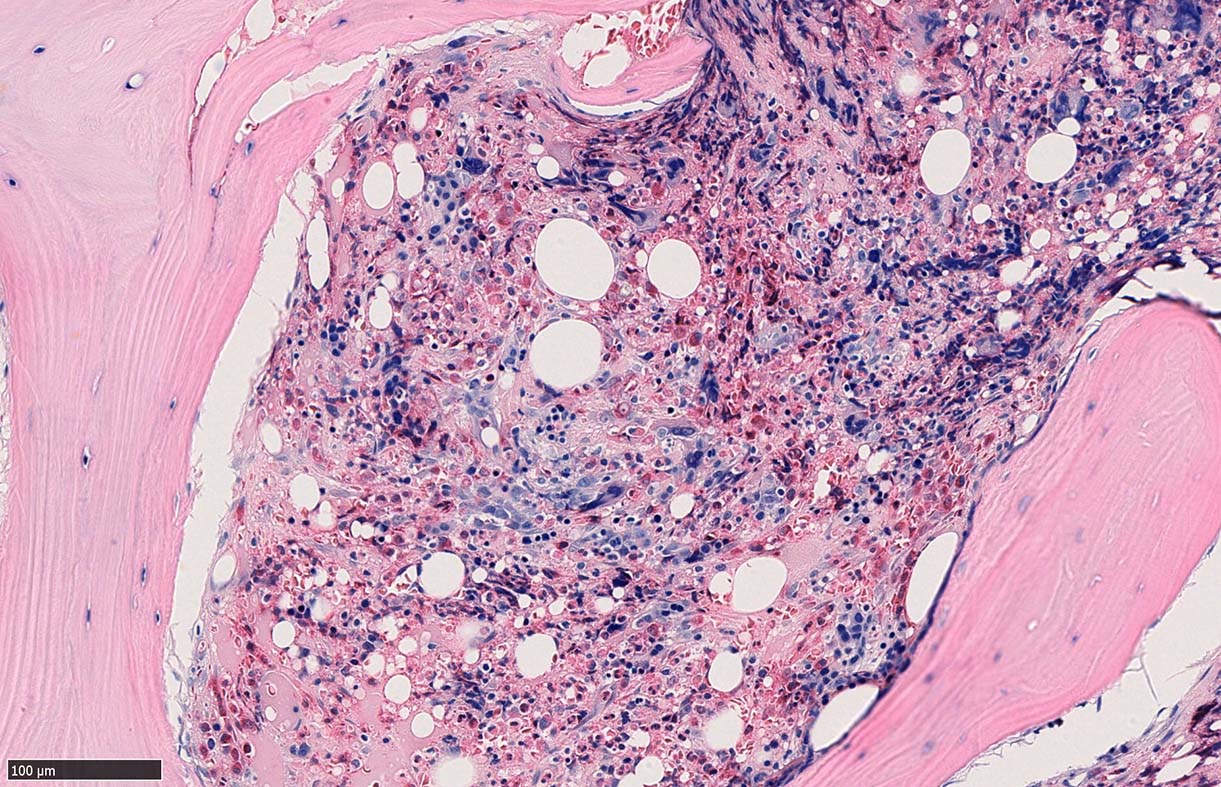

CD42b染色

骨髄組織所見 bone marrow biopsy total 6mm in length

塗銀染色